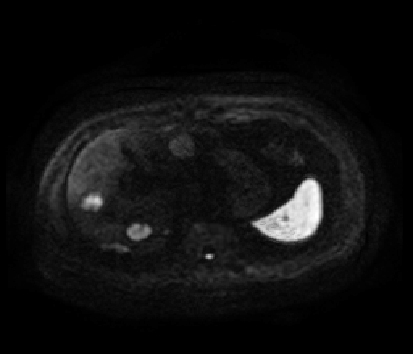

2017-06-20肝脏MRI增强:肝内多发占位,考虑MT。

2017-6-20肝脏MRI增强

2017.10.17复查肝脏MRI增强:肝脏多发转移瘤,较2017-06-20进展。

间隔4月MRI比较:

2017.06.20MRI

2017.10.17MRI

PD

2017.12.26CT

PR